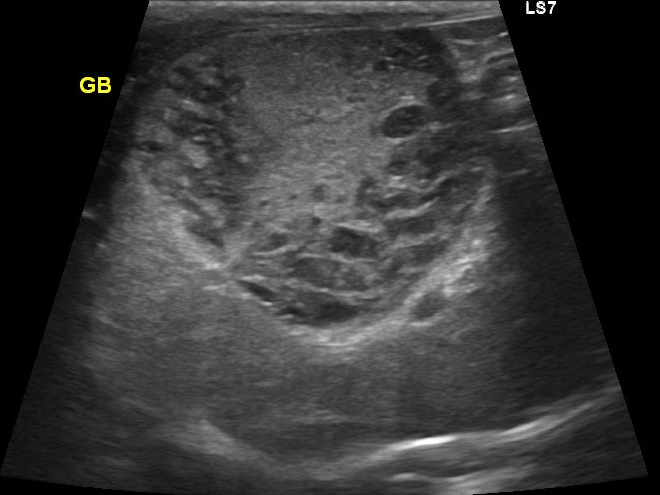

エコー検査では胆嚢の中を満たすほど胆泥が溜まっています。

このままにしておくと胆嚢がいつ破裂するか分かりません。

エコーで胆嚢炎と胆嚢粘液嚢腫であることを確認し、破裂の危険性を考えて腹腔鏡下胆嚢摘出術を実施することになりました。